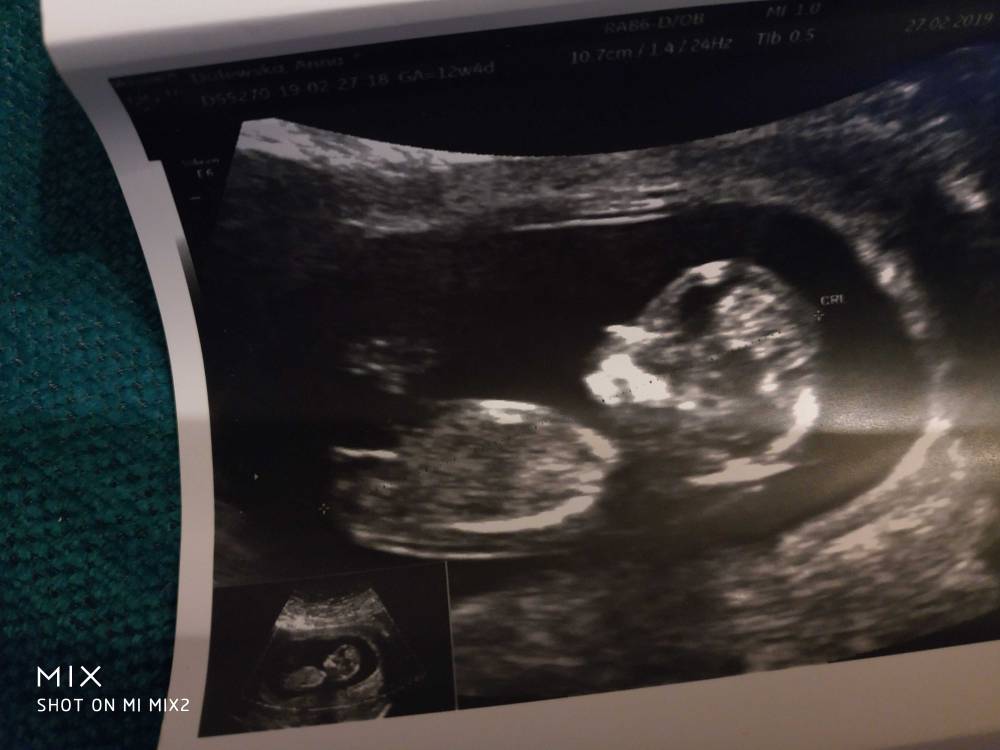

Hej dziewczynki melduje że wszystko ok [emoji6] dzidzia piękna, prawie 6cm, piękny nosek. Chyba spała, z początku się wystraszyłam że coś się dzieje ale lekarz puścił serduszko i pięknie bije. Przepływy dobre, Nt wyszło lekko podwyższone bo 2,36mm ale razem z innymi wynikami wychodzi dobrze. Ryzyko wg USG też wyszło ok. Za dwa tyg będą wyniki z krwii. Doktor powiedział że z USG maluch zdrowy. No i na 70% będzie dziewczynka [emoji7][emoji7] ale póki co się nie nastawiać [emoji6] zdjęć dostaliśmy tyle z tego jednego USG że przez całą ciążę z synem tyle nie miałam [emoji23]

Zobacz załącznik 947066Zobacz załącznik 947067